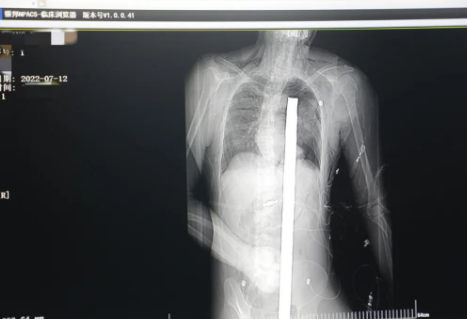

1.2米長(zhǎng)的鋼筋貫穿男子胸腹!情況極度危險(xiǎn)......

突發(fā)!太疼了,1.2米長(zhǎng)的螺紋鋼從男子會(huì)陰部垂直穿入胸腔......7月12日下午16時(shí)10分,西安一處工地的一名26歲工友,不慎從10多米的高空墜落,不幸的是工地上一根直徑3厘米的螺紋鋼從男子會(huì)陰部垂直穿入體內(nèi),工地上的工友們小心翼翼地將連著的鋼筋截?cái)?。情況危急,立即送往西安國(guó)際醫(yī)學(xué)中心醫(yī)院急救中心,此時(shí)正是下午17時(shí)00分。

時(shí)間就是生命!此時(shí),西安國(guó)際醫(yī)學(xué)中心醫(yī)院展開了一場(chǎng)與生命賽跑的搶救,第一時(shí)間開辟綠色通道,急診X光片及CT顯示:異物經(jīng)會(huì)陰部貫穿盆腔、腹腔到達(dá)左側(cè)胸腔主動(dòng)脈弓水平。醫(yī)院創(chuàng)傷中心立即啟動(dòng)應(yīng)急預(yù)案,劉延彤副院長(zhǎng)親臨指揮,下午17點(diǎn)48分,當(dāng)患者被送達(dá)手術(shù)室,胸外、心外、肝膽外科、胃腸外科,泌尿外科及麻醉科等多學(xué)科專家聯(lián)手對(duì)這名工友進(jìn)行“縱劈胸骨 前外側(cè)開胸探查 氣管及主支氣管修補(bǔ) 肺修補(bǔ) 血胸清除 開腹探查止血 腹膜后及盆腔探查......”手術(shù)。

情況緊急!術(shù)中探查后發(fā)現(xiàn),長(zhǎng)120cm直徑3cm的螺紋鋼經(jīng)患者右側(cè)會(huì)陰部穿入,傷及直腸,途徑膀胱后方,左側(cè)髂總動(dòng)靜脈之間傷及左腎后,經(jīng)胰腺后方在肝脾之間穿破膈肌,在下肺靜脈前方穿入左肺穿破氣管及左右主支氣管膜部,止于主動(dòng)脈弓下水平,穿入體內(nèi)的部分達(dá)到75cm。